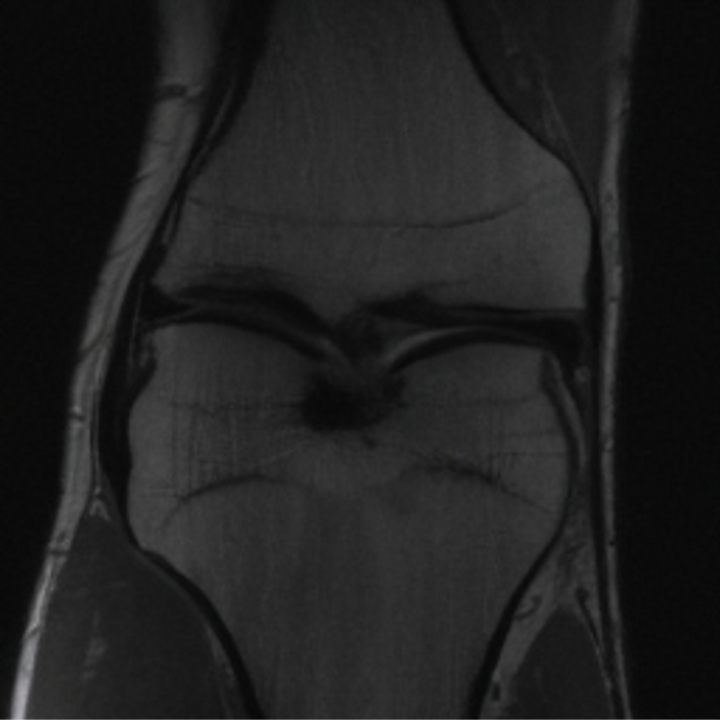

5.3 Out-of-Domain Generalisation

One way to test the generalization capability of the trained X-Diffusion is to test it on a completely different domain from an MRI dataset not seen during training. We report the single-slice results on NYU fastMRI [37, 82], a knee MRI dataset, using the X-Diffusion trained on the BRATS brain MRIs. The results are shown in Figure 9 and Table 2. It shows how successfully X-Diffusion is able to generate knee MRIs from a single image, despite not seeing knees at all in training. To qualitatively assess how realistic our generated 3D volumes were (produced from a single slice), we gave 20 generated examples alongside their real MRI counterparts to an expert orthopaedic surgeon. He was then asked to identify the real example from a given pair. The surgeon identified with certainty only 10 real knee MRIs out of 17, while could not decide on the remaining 3 of the 20 MRI pairs. This further validates the generated out-of-domain MRIs.

In this work, we present X-Diffusion, a cross-sectional diffusion model tailored for Magnetic Resonance Imaging (MRI) data. X-Diffusion is capable of generating the entire MRI volume from just a single MRI slice or optionally from few multiple slices, setting new benchmarks in the precision of synthesized MRIs from extremely sparse observations. The uniqueness lies in the novel view-conditional training and inference of X-Diffusion on MRI volumes, allowing for generalized MRI learning. Our evaluations span both brain tumour MRIs from the BRATS dataset and full-body MRIs from the UK Biobank dataset. Utilizing the paired pre-registered Dual-energy X-ray Absorptiometry (DXA) and MRI modalities in the UK Biobank dataset, X-Diffusion is able to generate detailed 3D MRI volume from a single full-body DXA. Remarkably, the resultant MRIs not only stand out in precision on unseen examples (surpassing state-of-the-art results by large margins) but also flawlessly retain essential features of the original MRI, including tumour profiles, spine curvature, brain volume, and beyond. Furthermore, the trained X-Diffusion model on the MRI datasets attains a generalization capacity out-of-domain (e.g. generating knee MRIs even though it is trained on brains). The code is available on the project website https://emmanuelleb985.github.io/XDiffusion/.

Contributions: (i) We introduce X-Diffusion, a cross-sectional diffusion model that generates MRI slices conditioned on a single input MRI slice or multiple slices. The proposed X-Diffusion achieves state-of-the-art results on MRI reconstruction and super-resolution compared to recent methods on BRATS, a large public dataset of annotated MRIs for brain tumours. (ii) We adapt our X-Diffusion to leverage paired and registered full-body MRI and DXA images from UK Biobank dataset to generate full-body 3D MRI from a single DXA for the first time in the literature. (iii) We validate the generated MRIs on a wide range of tasks that ensure the generated MRIs retain important features of the original MRIs, including tumor profiles, spine curvature, brain volume, and more, without using this meta-information in the generation process. (iv) We showcase the generalization of trained X-Diffusion on different datasets (knee MRIs) illustrating the potential of X-Diffusion to be the first 3D volumetric foundation model in medical imaging.